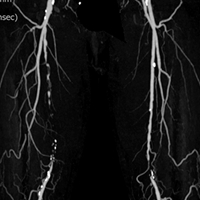

豊橋ライブのEVTセッションには欠かせない3名のEVTマスターオペレーターと接点のある演者が「マスターの技術が伝承されているのか?」をテーマにプレゼンし、マスターとの考え方の一致する点、一致しない点をディスカッションするセッションです。